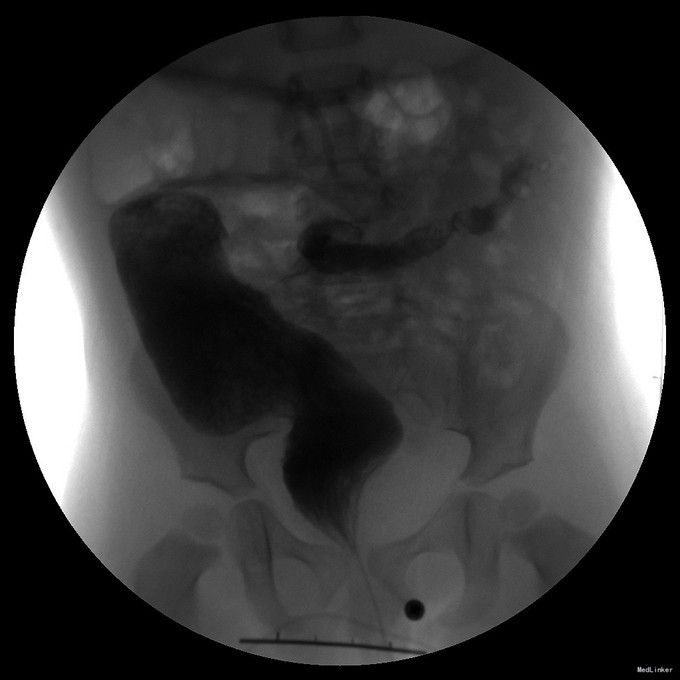

查体: 腹部稍膨隆,未见肠型及胃肠蠕动波,肛门指检稍狭窄,直肠壶腹空虚,退出指套无血染,无明显刺激性排气排便。 辅查: 钡灌肠:乙状结肠扩张,内见粪石。

诊断:肛门狭窄术后继发性巨结肠 治疗:完善术前准备,全麻下行腹腔镜下经肛门继发性巨结肠根治术,术中见肛门往内回缩,肛周瘢痕增生明显,直肠下段扩张明显,术后给予积极抗感染补液治疗。